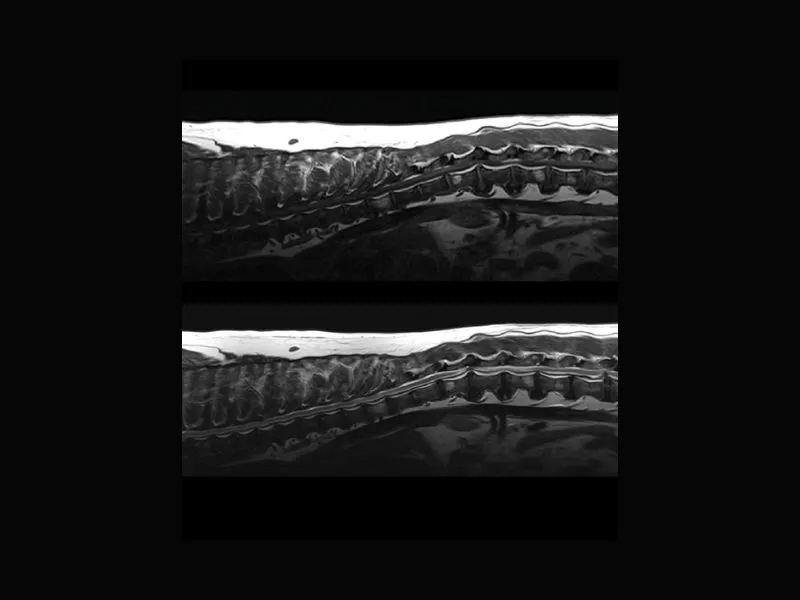

Clinical images

Small animals